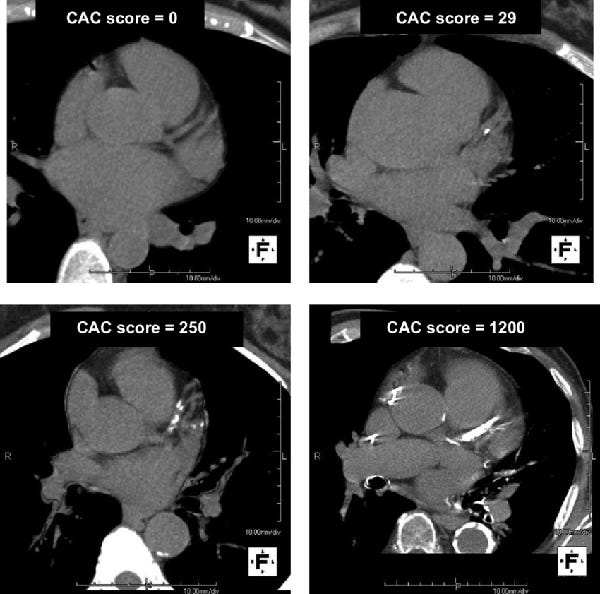

Coronary Calcium Score - Capital Heart Centre

www.capitalheart.sg

www.capitalheart.sg